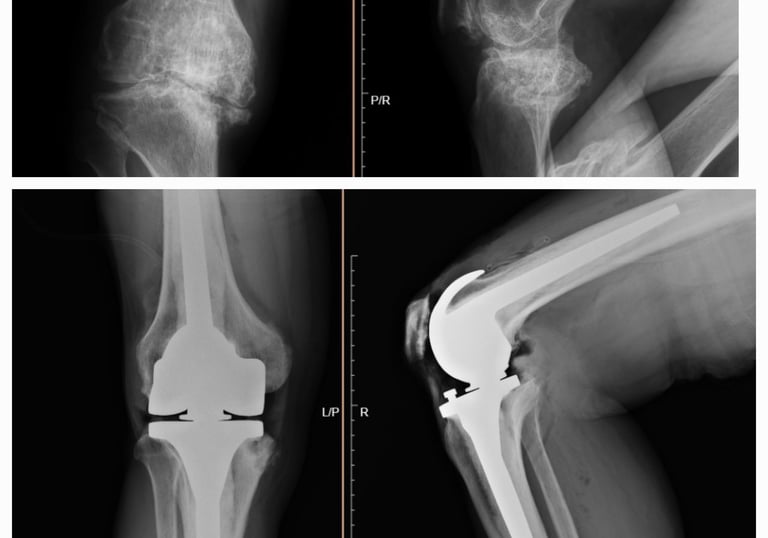

Tratamiento de lesiones severas de rodilla

Diagnóstico y tratamiento de daños importantes en ligamentos, meniscos, cartílago o hueso que afectan la estabilidad y movimiento de la rodilla. Dependiendo de la gravedad, puede requerir cirugía reconstructiva o reemplazo articular, siempre con el objetivo de recuperar la función, disminuir el dolor y permitir que el paciente retome sus actividades diarias o deportivas.

Cirugía en la que se reemplaza la articulación dañada por una prótesis nueva. Se realiza en casos de desgaste severo, artrosis o lesiones que provocan dolor intenso y limitan la movilidad. El objetivo es devolver la capacidad de caminar, realizar actividades cotidianas sin dolor y mejorar la calidad de vida.

Prótesis de cadera y rodilla